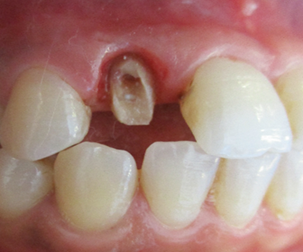

The level of vestibular damage is slightly subgingival. The prosthetic treatment plan consisted of fabricating a zirconia crown after coronoradicular reconstruc-tion. The patient decided to keep the diastemas. The removal of carious tissue and endodontic retreatment were performed (Figure 3).

Figure 3: Post-operative photograph.